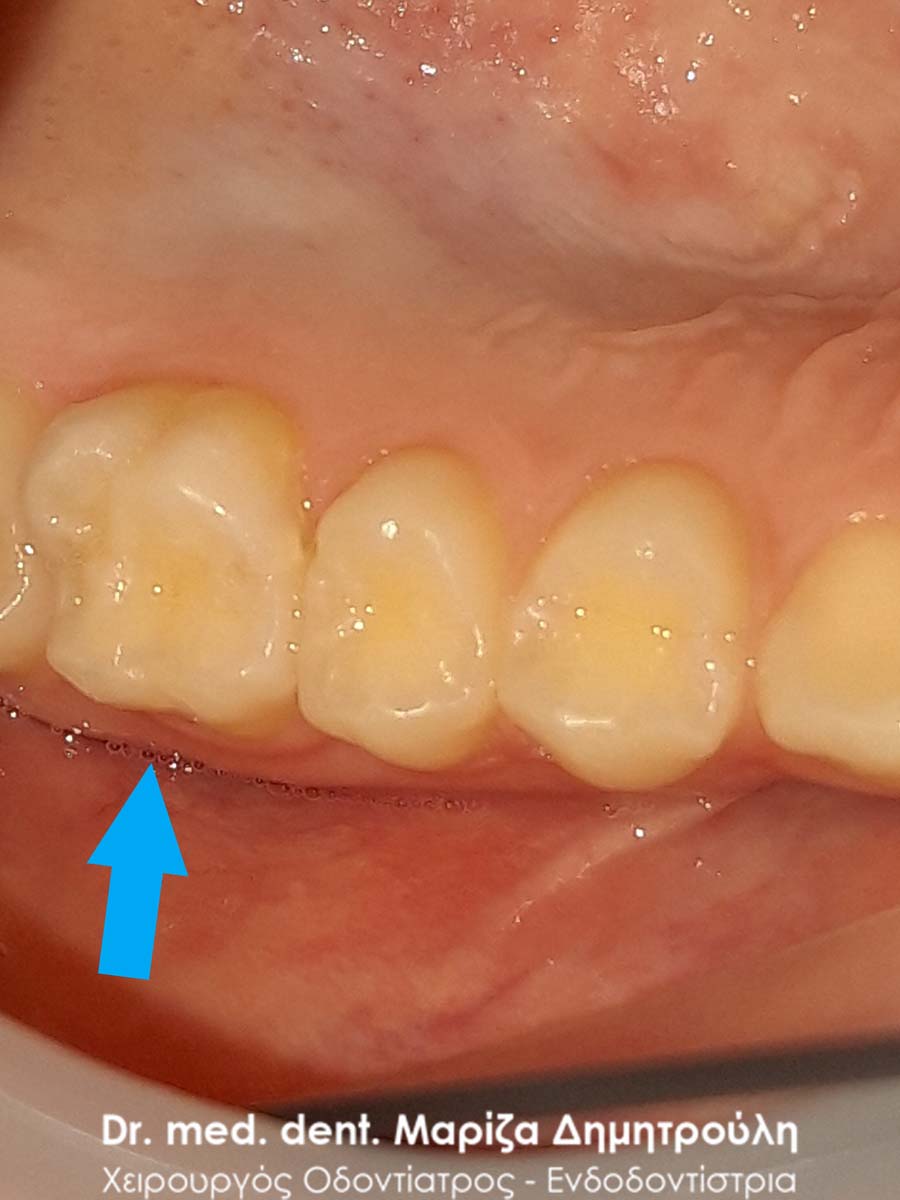

ΠΡΙΝ

ΜΕΤΑ